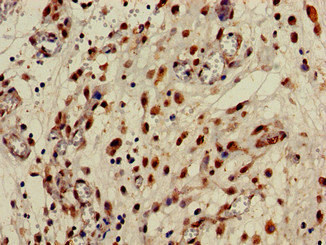

Immunohistochemistry of paraffin-embedded human lung cancer using CSB-PA005884LA01HU at dilution of 1:100